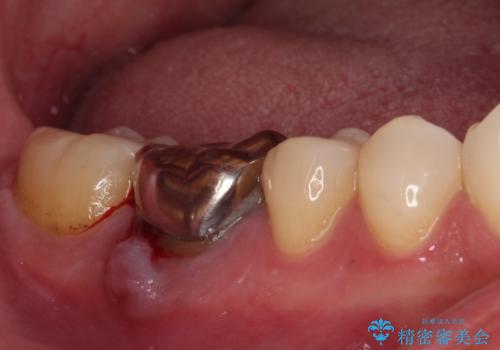

- 右下の奥歯の歯茎が腫れているとのことで来院された患者様です。

銀のクラウンが装着されていた歯は根管治療が必要であり、その奥の歯は大きな詰め物の隙間が虫歯になってしみていました。

根管治療などを行った後に、オールセラミッククラウンにて補綴することとしました。